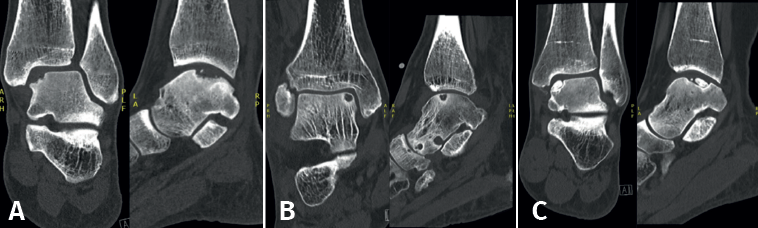

Fixation techniques have shown clinical and radiological success in 8 out of 10 patients, also maintaining their success in the long term (Figures 5 and 6). As these techniques preserve the hyaline cartilage and provide superior healing of the subchondral bone, they are advantageous over other surgical treatment options for OLTs, when feasible(39,41).